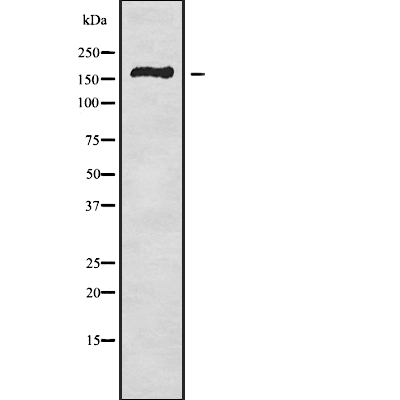

分类: 科研抗体货号: P42751别名: AII; AVP; FCU; MWS; FCAS; CIAS1; NALP3; C1orf7; CLR1.1; PYPAF1; AGTAVPRL应用: WB反应种属: Human